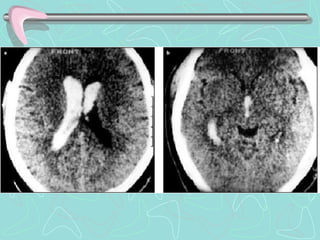

Early CT signs of infarction.

(a) Hyperdense right middle cerebral artery, suggesting intravascular occlusion by

thromboembolism.

(b) Loss of differentiation between gray and white matter. The left lentiform nucleus is

visible, as normal, as a slightly hyperdense structure (single arrow), but is absent on the

right (double arrow) because of edema from infarction.

(c) Large area of hypoattenuation (arrows),

Early ischemic signs.

(a). The insular ribbon sign is shown

(b) the lateral margin of the left putamen cannot be seen (short arrows).

(c) hyperdense embolic material in the middle cerebral artery stem (the ‘‘hyperdense MCA sign,’’).